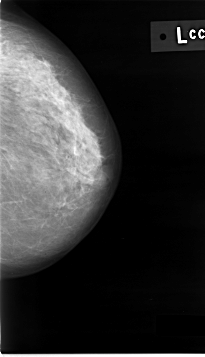

C_0012_1.LEFT_CC

LEFT_CC LINES 4632 PIXELS_PER_LINE 2656 BITS_PER_PIXEL 12 RESOLUTION 50 NON_OVERLAY